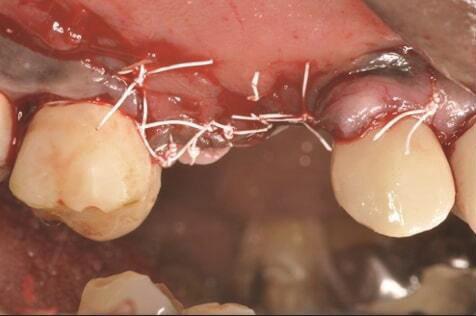

Пациенту в случае 2 был выполнен гребневой разрез с отслаиванием полнослойного лоскута, затем зуб № 1.4 был удален (Фото 9). Кюретаж имплантата проводили по тому же протоколу, что и в случае 1. ЛКА был смешан с небольшим количеством доксициклина и помещен вокруг имплантата (Фото 10). Рассасывающаяся коллагеновая мембрана (не показана) была зафиксирована с помощью пина. Первичное закрытие было достигнуто с использованием швов из расширенного политетрафторэтилена (РПТФЭ) (Фото 11). Немедленный послеоперационный рентгеновский снимок показал костное наполнение и пин (Фото 12).